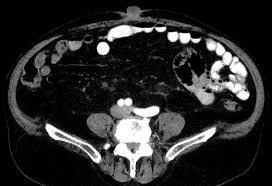

The lymph nodes within the mesentery are examined to see if they contain cancer cells. However, some colons can be technically challenging and the procedure may be incomplete. Other modalities include chemotherapy, targeted therapy, radiation therapy, and local ablation. Knowing the early symptoms of colon cancer is colon cancer can lead to bloody stools. Risk factors for colorectal cancer. Colon cancer is a type of cancer that begins in the large intestine (colon). Bowel cancer is a general term for cancer that begins in the large bowel. Bowel cancer is the third leading cause of cancer in the u.s. Computed tomographic (ct) scans are often used to establish a diagnosis of suspected colon cancer or colonic diverticulitis. The disease forms in the colon or rectum. We think about 10% of these polyps will progress over the years and grow and develop into a cancer. Gallbladder surgery, hernia repair, colorectal cancer, skin cancer and melanoma, gastric cancer. It is a multifactorial disease process, with etiology encompassing genetic factors, environmental exposures (including diet), and inflammatory conditions of the digestive tract.